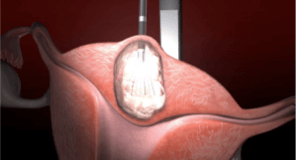

The Acessa procedure offers optimized technology for more complete fibroid treatment, provides relief with low reintervention, and allows you to care for more patients by offering more uterine sparing options. Using controlled radiofrequency energy (heat), the Acessa procedure causes coagulative necrosis of the fibroid tissue. The treated tissue softens and shrinks over time, allowing fibroid symptoms to resolve without difficult and time-consuming uterine suturing.1